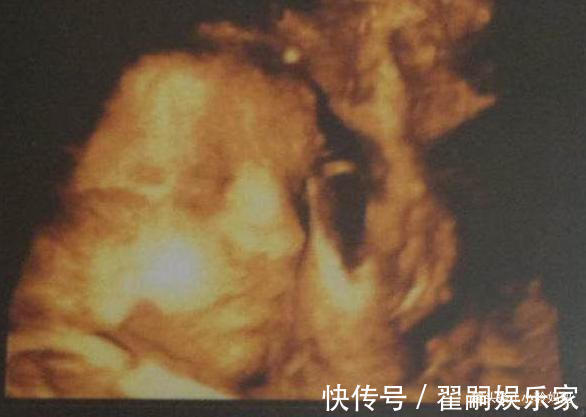

一位怀孕7个月的孕妈去产检,在前6个月的时候,一切正常,胎儿发育的很健康,但是到了第7个月的时候,就发现胎儿在孕妈肚子里“捂着鼻子”,并且表情也有些痛苦。医生非常惊讶,从事医生这个行业这么多年,但是却没有见过这样的胎像,由于胎儿异常,医生断定肯定是出现了问题,所以便开始查找原因,询问孕妈这段时间都做了什么。